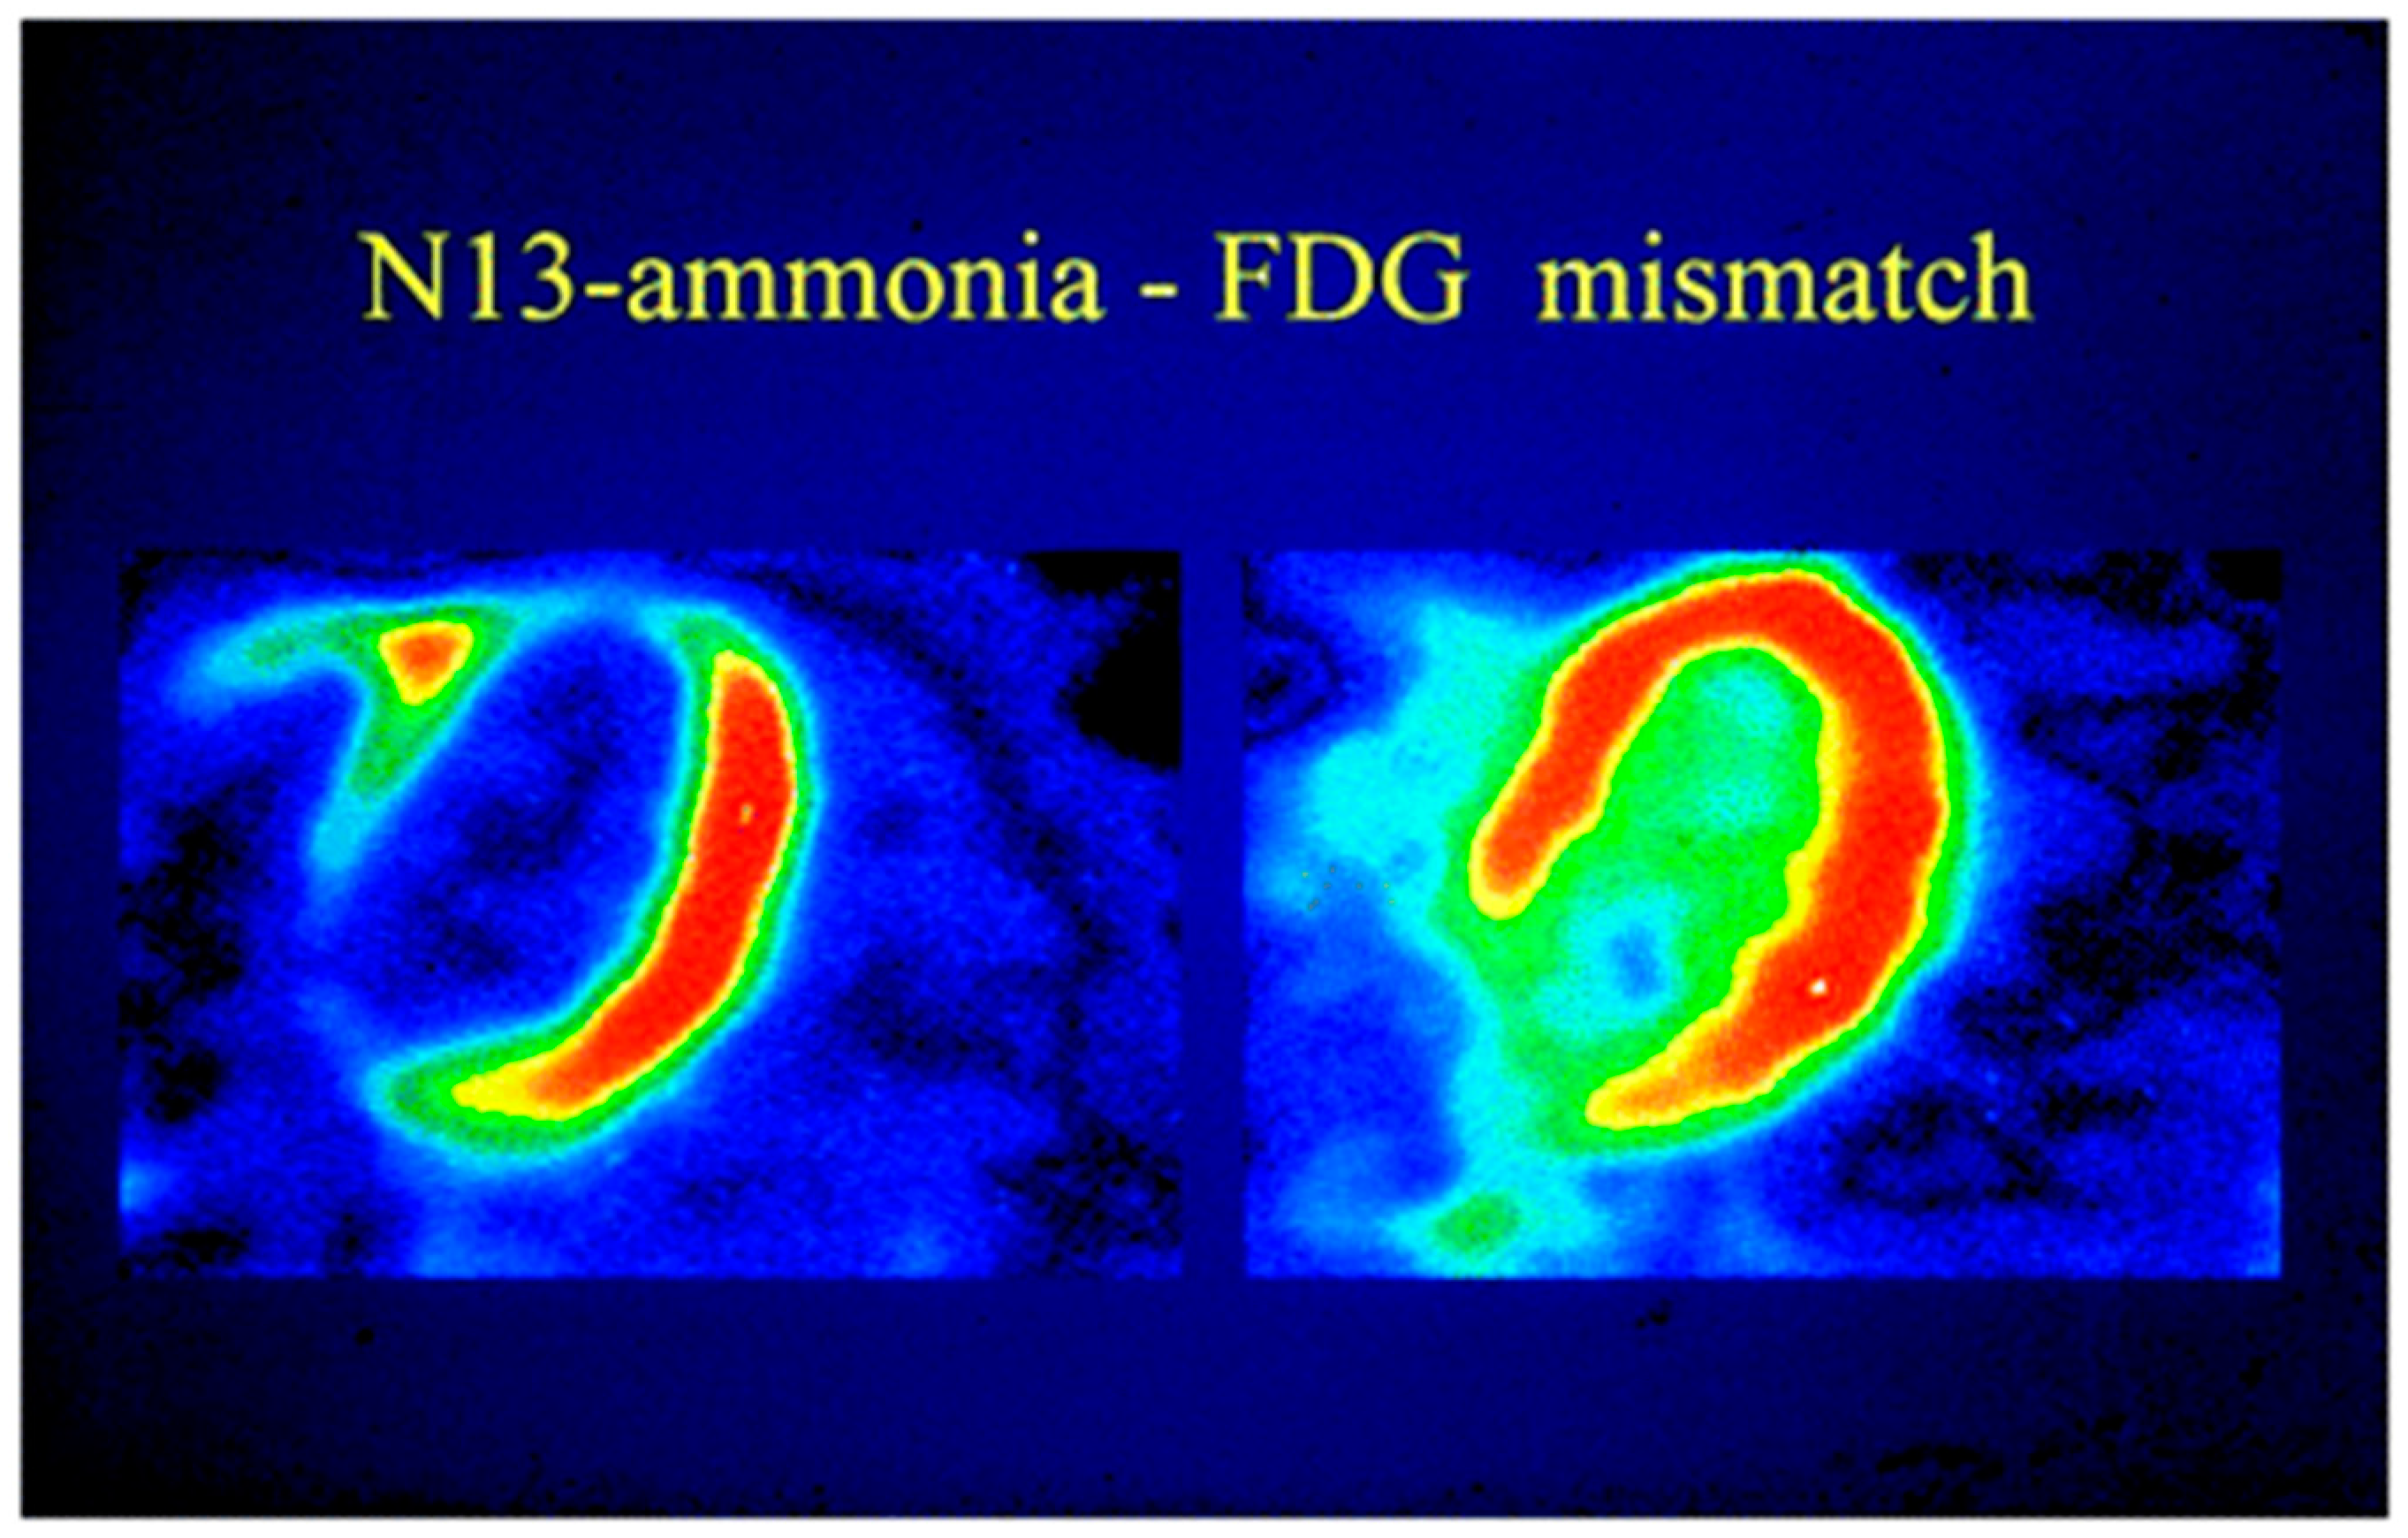

3.2. Myocardial Metabolism and Viability

5.2. Viability and Infarct Assessment